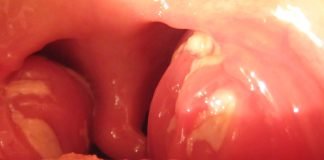

Amigdalita la copii: simptome, cauze si remedii

Poate una dintre cele mai frecvent intalnite afectiuni la copii este amigdalita, care, de fapt, este o inflamatie a amigdalelor, desi cauza directa poate...